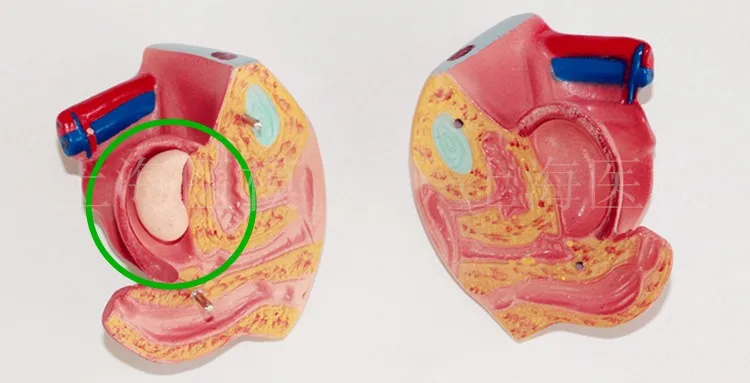

45CM uniex human Torso human anatomical structure model internal organ model 23 parts